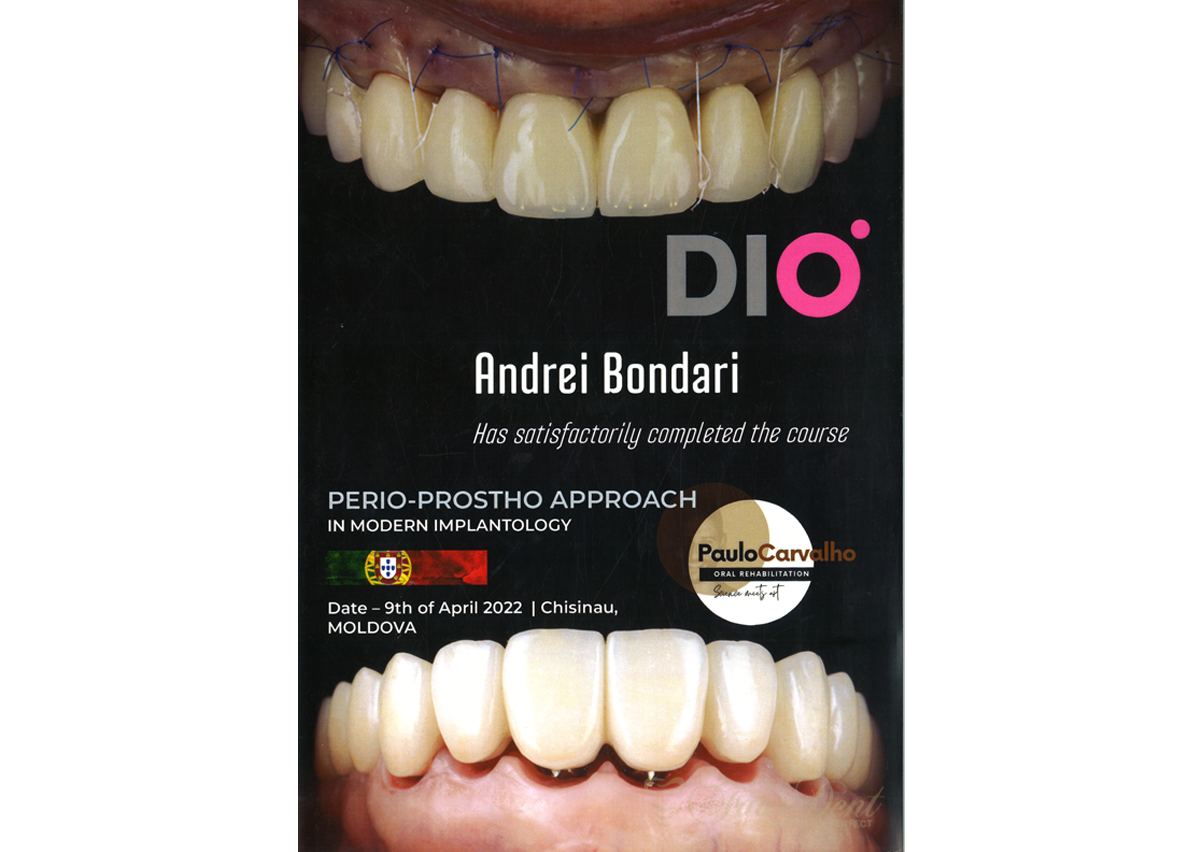

Experiență, profesionalism și tehnologie modernă pentru zâmbetul tău perfect în Chișinău, Buiucani. Descoperă serviciile noastre de dantură fixă sau programează-te pentru o consultație.

Specialiști cu experiență